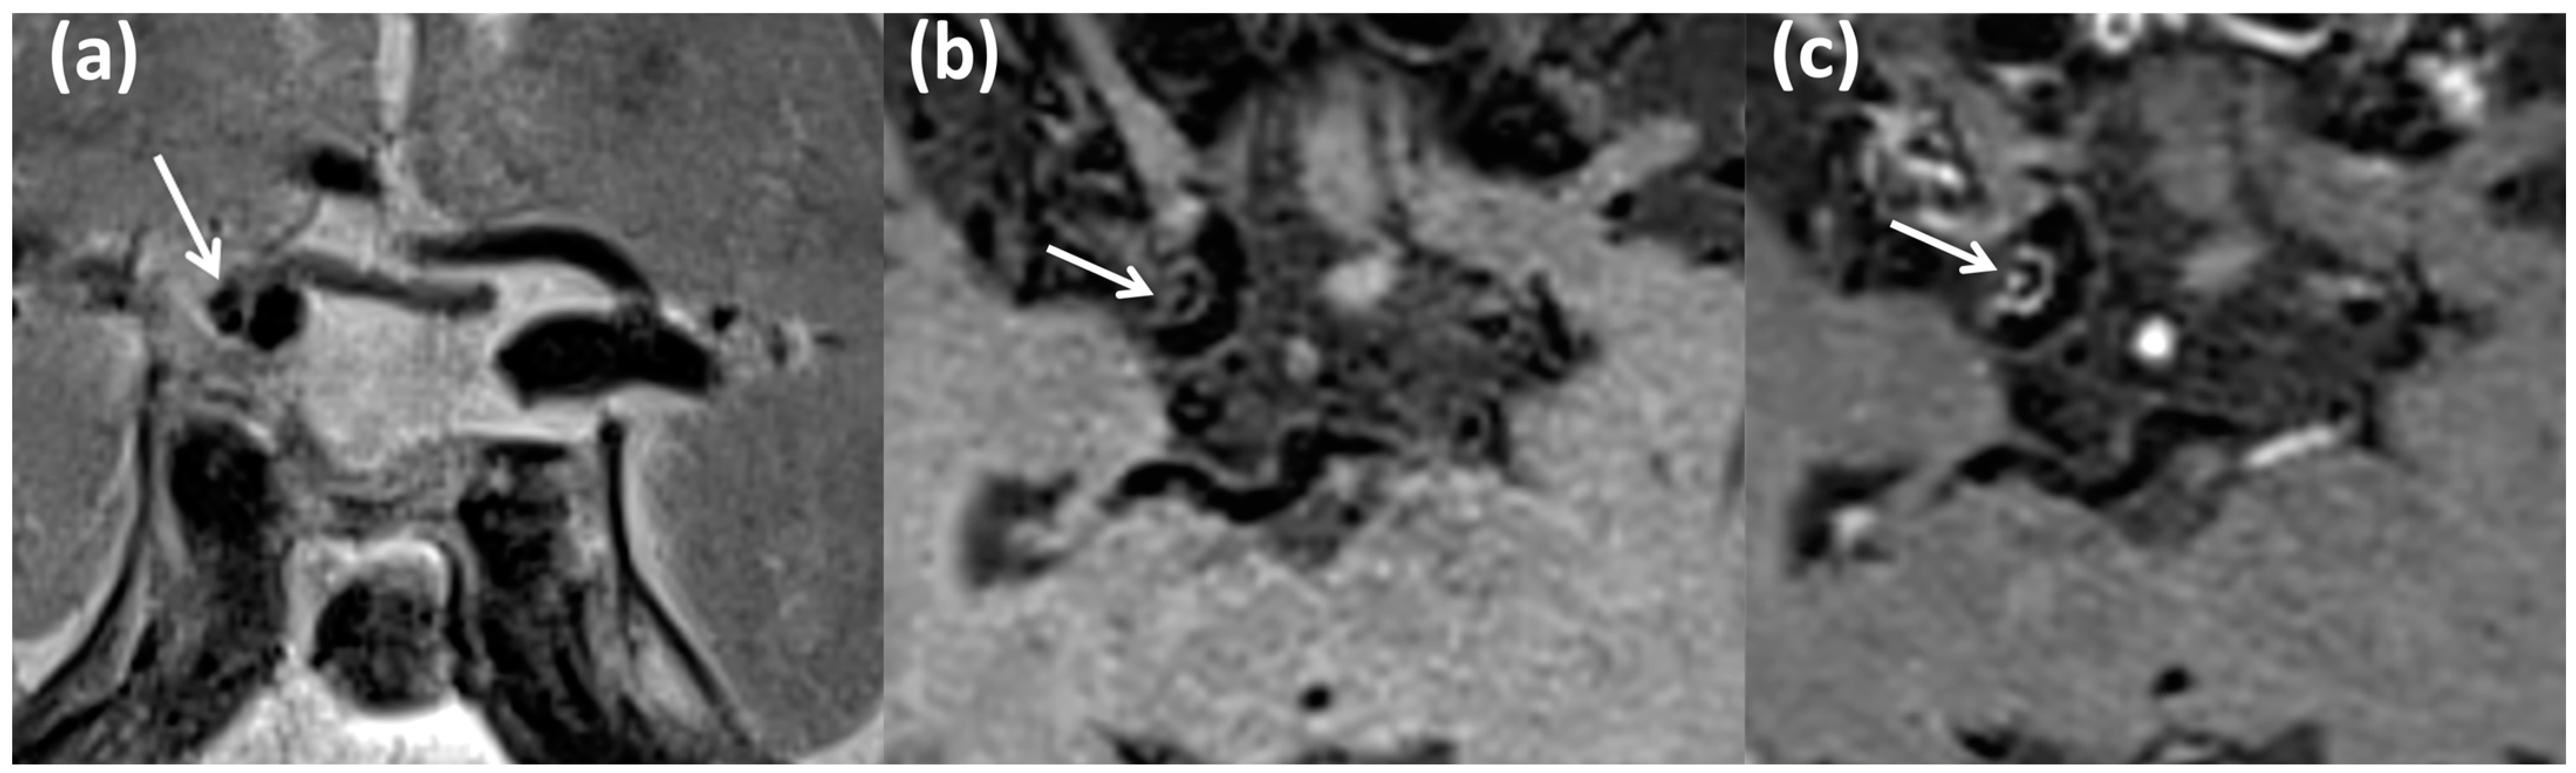

2. Materials and Methods

2.1. Study Population